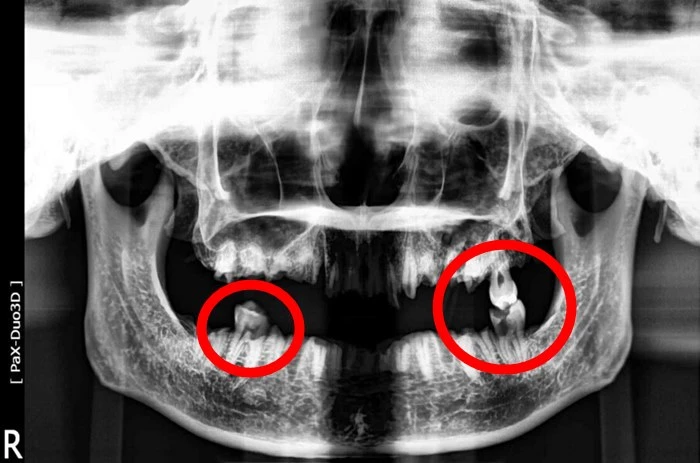

인천 계양경찰서가 추가로 공개한 사진

23일 인천 계양경찰서는 훼손 시신 두개골의 치아 파노라마 사진을 추가로 공개했다. 해당 사진을 보면 시신 두개골에는 치아가 3개만 남아있다.

경찰은 치아 3개를 제외한 나머지 치아 상당수는 고의 훼손 등으로 남아 있지 않는 것으로 추정했다. 기계 등을 이용해 치아를 고의로 절단한 듯한 흔적이 사진에서 발견됐다.

위턱(상악) 왼쪽 치아에는 금 인레이, 아래턱(하악) 왼쪽과 오른쪽 치아에는 레진 치료를 받은 흔적이 있는 것으로 전해졌다. 해당 치아에서 신경치료 흔적은 보이지 않았다.

경찰은 사망자가 치과 치료를 주기적으로 받아왔던 것으로 보고 있다. 따라서 경찰은 치과 등 병원의 관련 기록을 토대로 도움을 줄 수 있는 관련 종사자들의 협조가 절실한 상황이다.